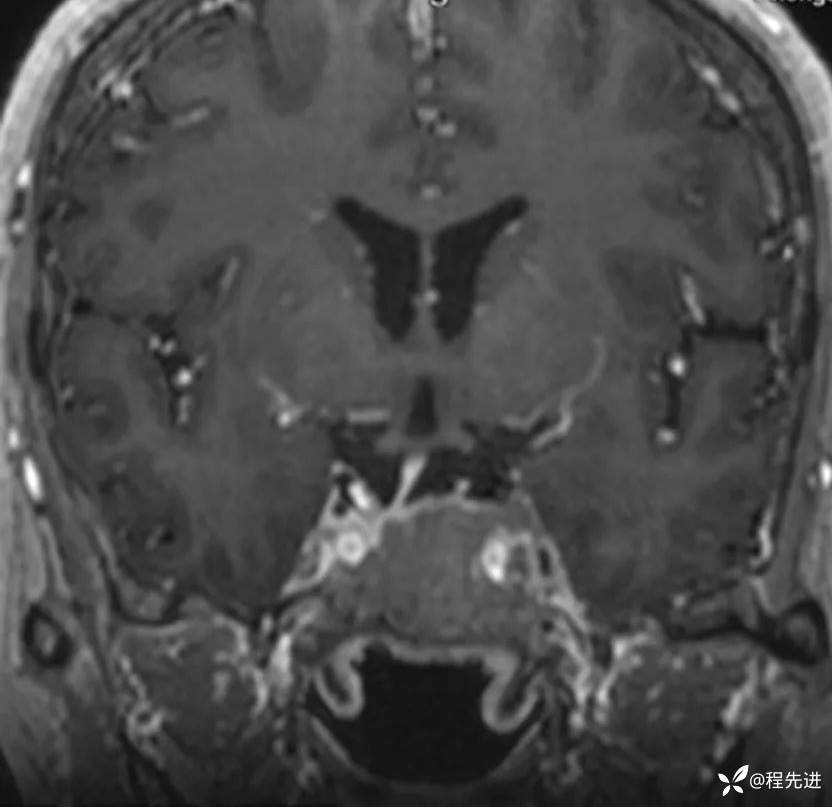

患者性别:女

患者年龄:63岁

简要病史:外伤检查发现颅底占位

CT增强:

MRI平扫+增强: